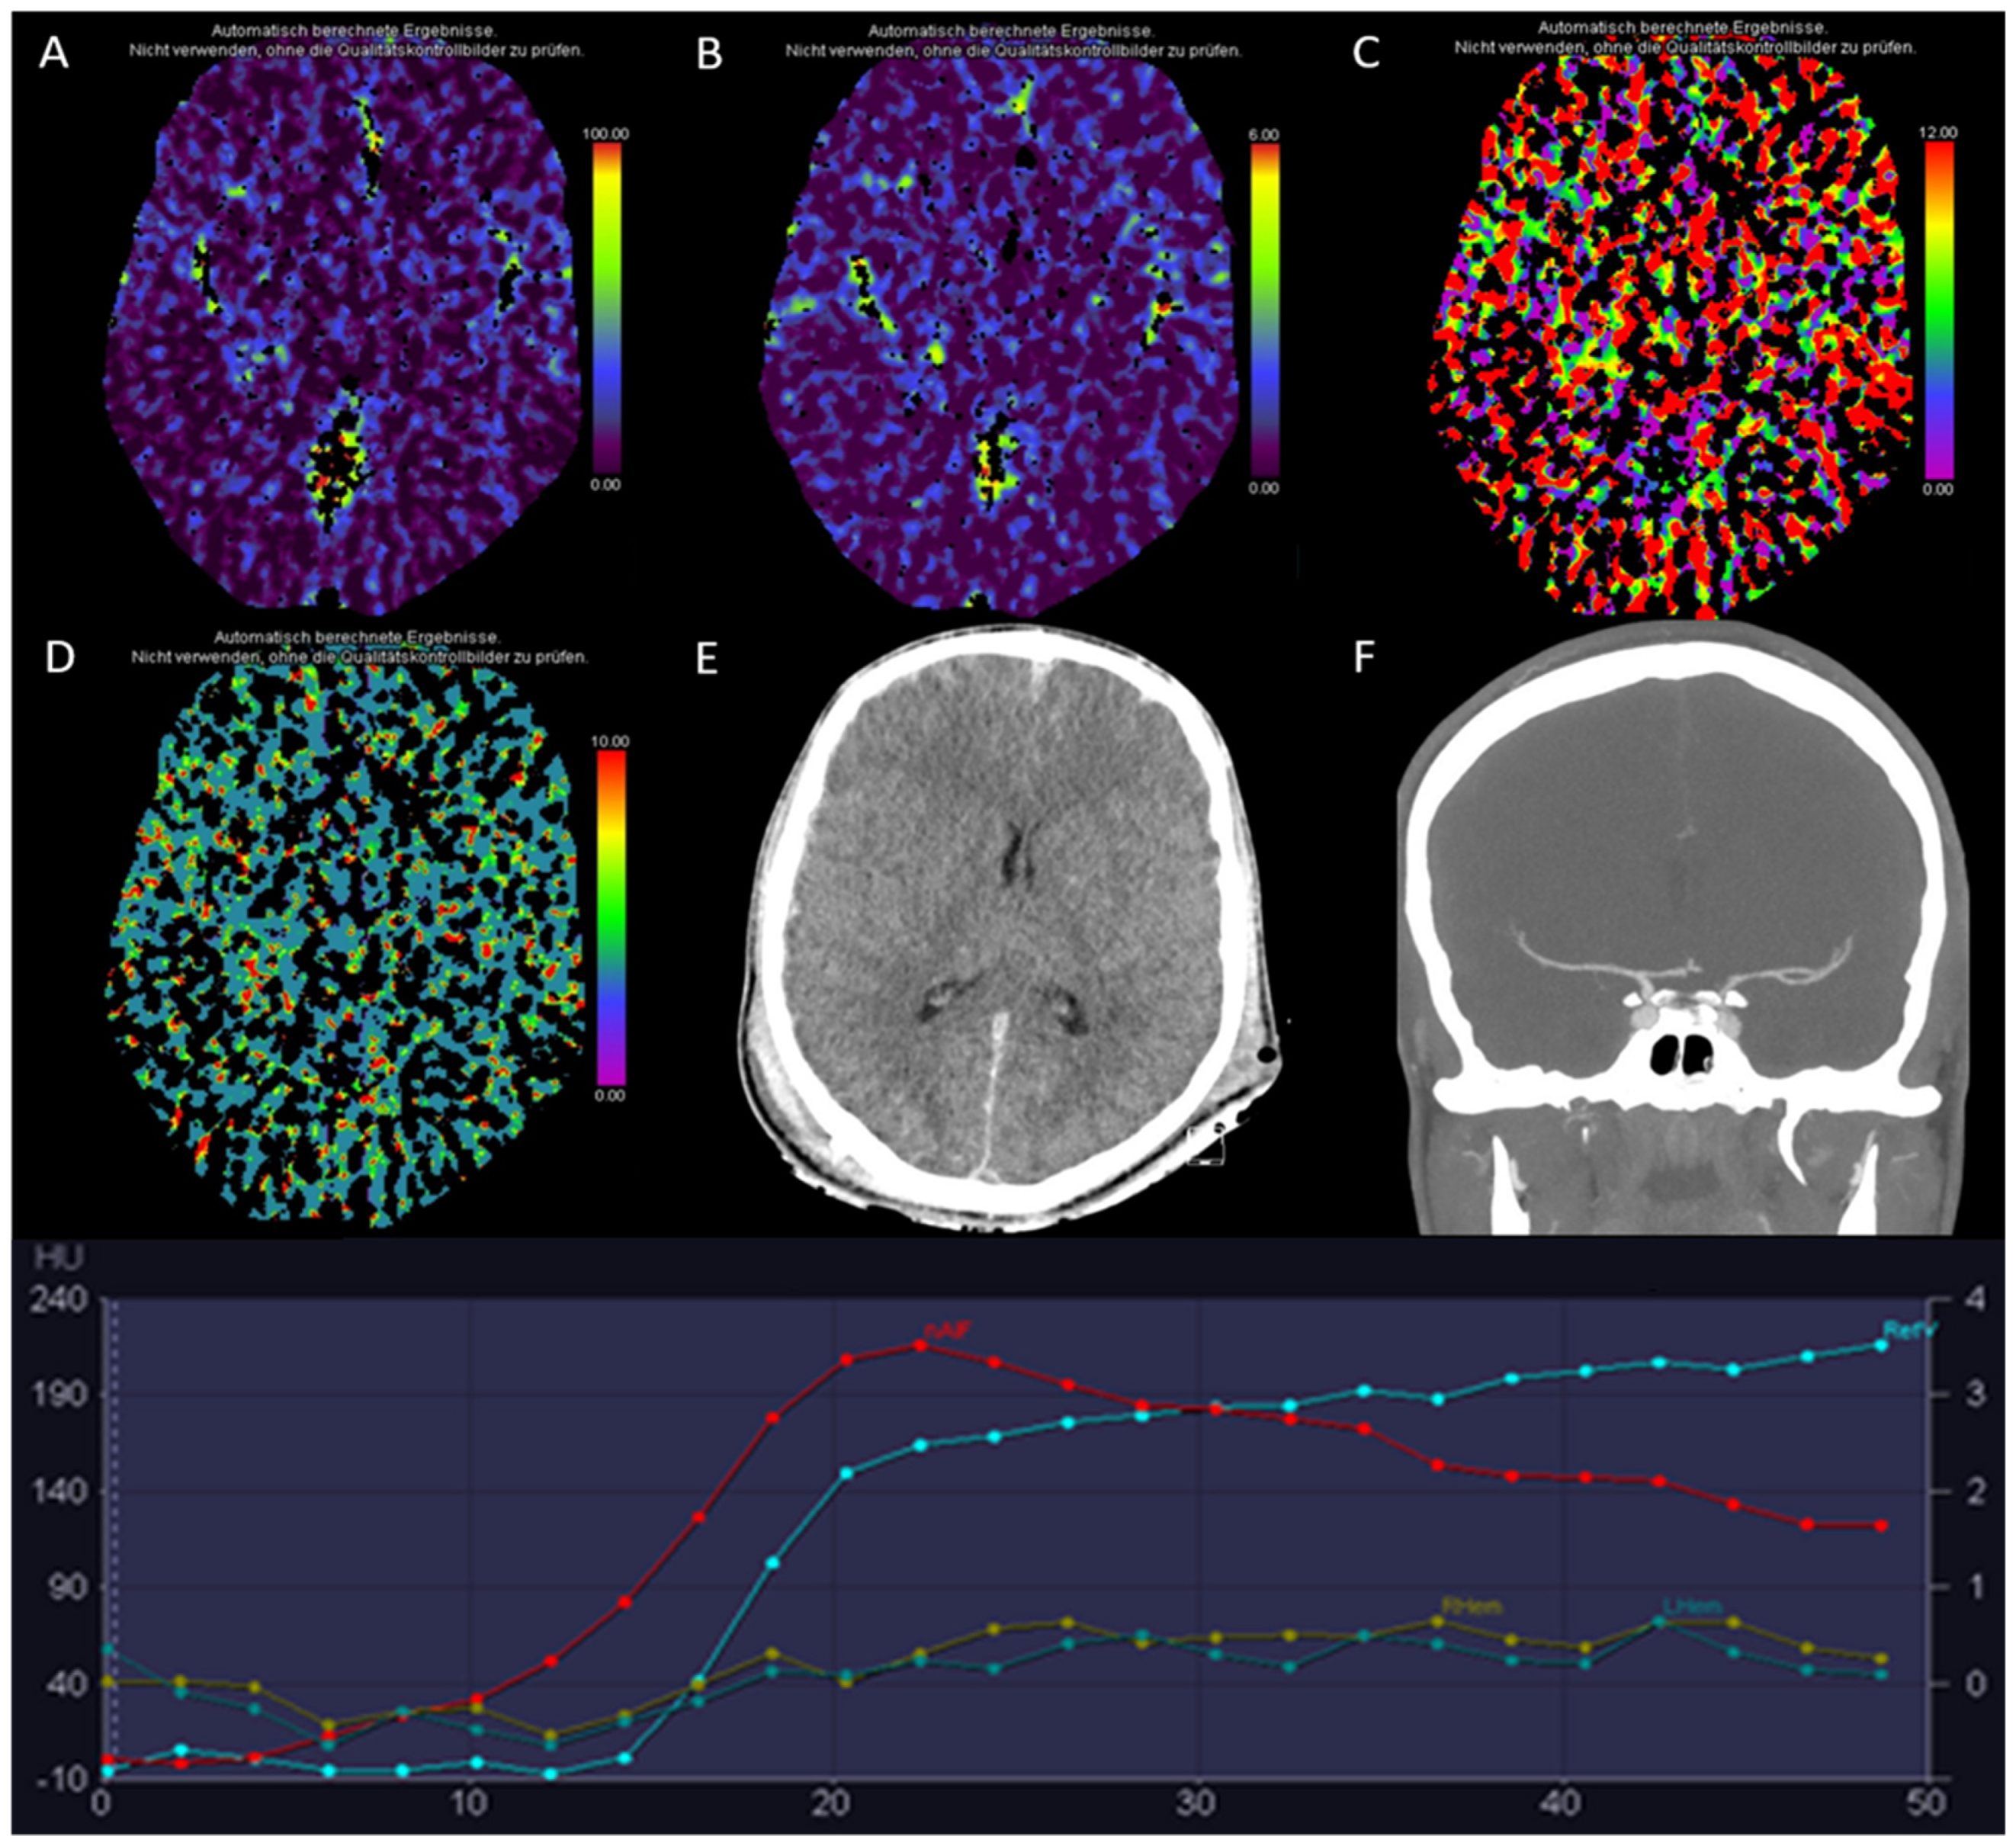

3.3. Global Hypoxic-Ischemic Injury/Brain Death